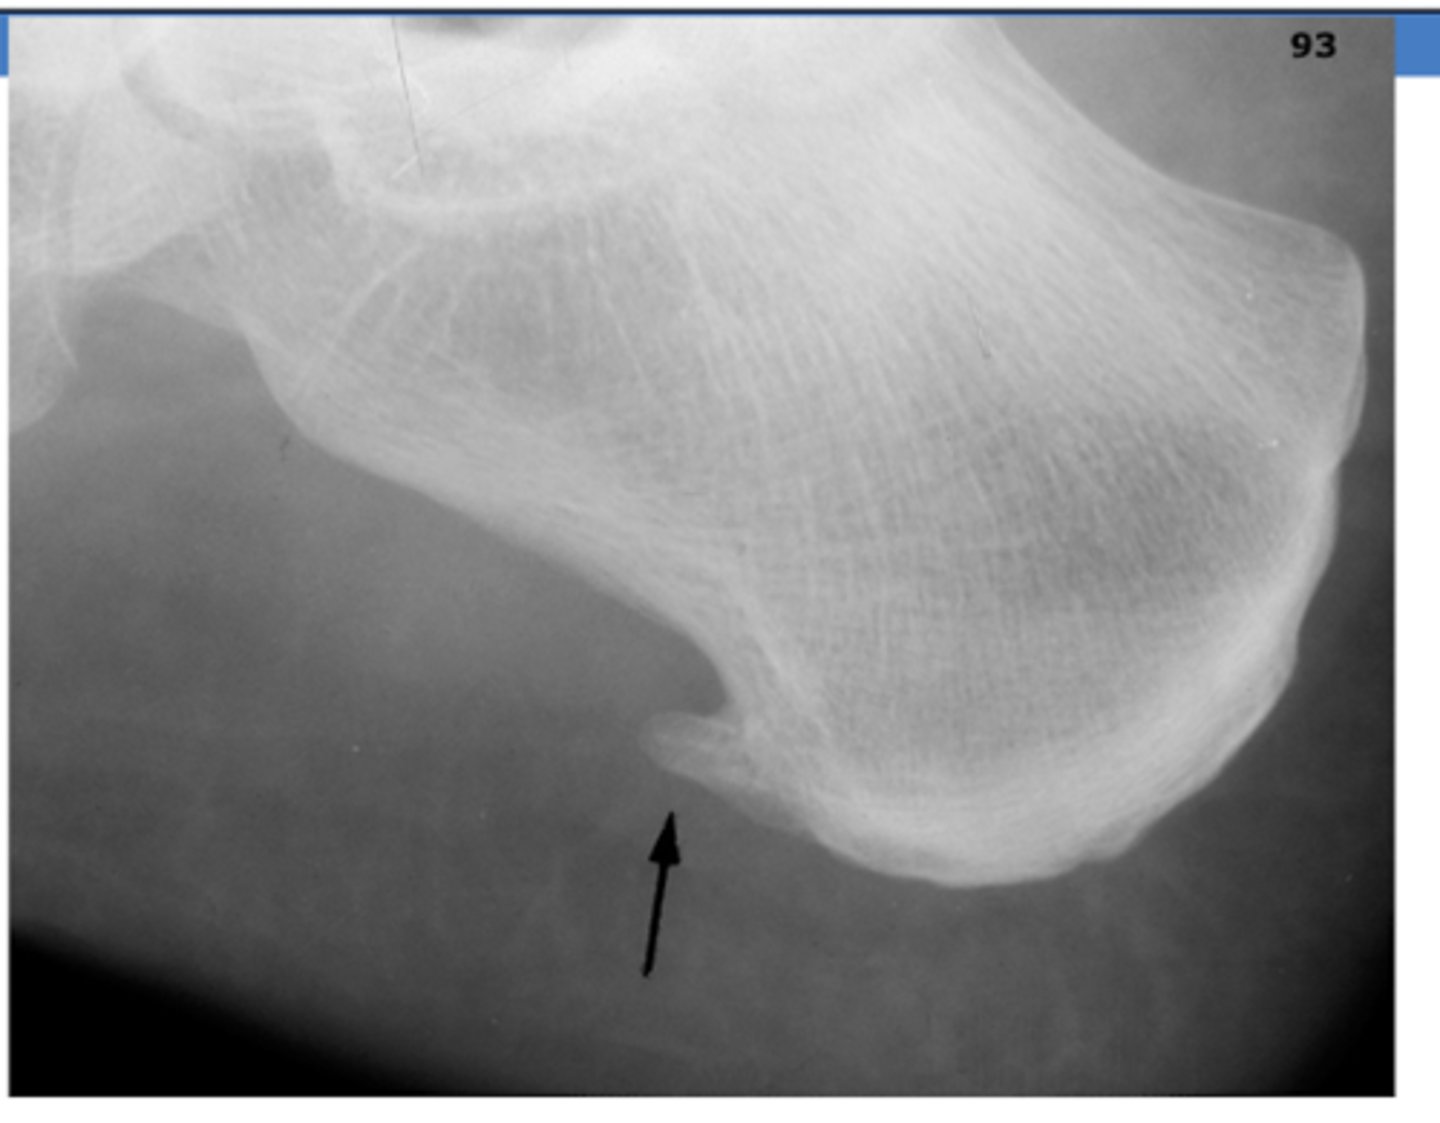

If a patient presents with heel pain and ecchymosis following fall/jump, what could be a possible diagnosis?

calcaneus fracture